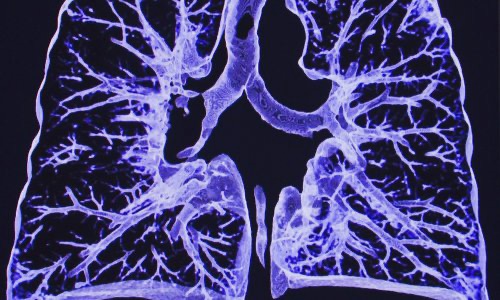

Radiografias De Torax A Traves De Vidrio En Pacientes Con Covid Everything Rad

www.carestream.com

Secuelas Del Coronavirus Recuperados Pero Con Pulmones Danados Dialogo Pandemico Preguntale A Dr Drexler Dw 20 03 2020

www.dw.com

Estos Son Los Pulmones De Un Joven Con Covid La Neblina Que Convirtio A Jose Pablo En Un Viejo

www.elespanol.com